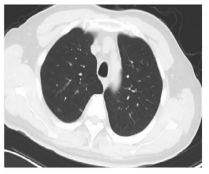

胸部CT:可见气道壁增厚、管腔轻度狭窄、气道壁少量渗出,存在中心性支气管扩张征象及双肺散在磨玻璃样浸润影。